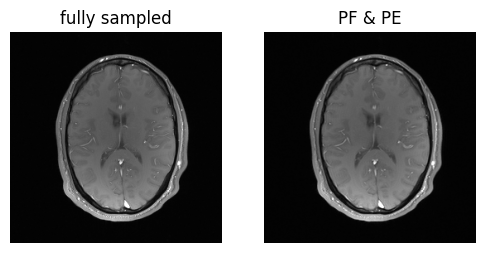

show_images(magnitude_fully_sampled, magnitude_pe_pf, titles=['fully sampled', 'PF & PE'])

../_images/cc47ebc8fa8fd128d8a4ad40415b00572f6dd4fdd5e2712d5bc085b652ebdd41.png

Voila! We’ve got the same brains, and they’re the same size!